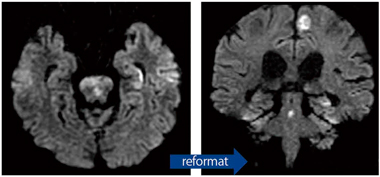

アイソトロピック3D FSE撮像法"Cube"におけるT1強調撮像が可能となった。短時間での高いコントラストによる3D T1強調画像を得ることが可能となった(図7)。

サジタルによるデータ収集からのreformat(撮像時間4分17秒)

(画像ご提供:琉球大学病院様)